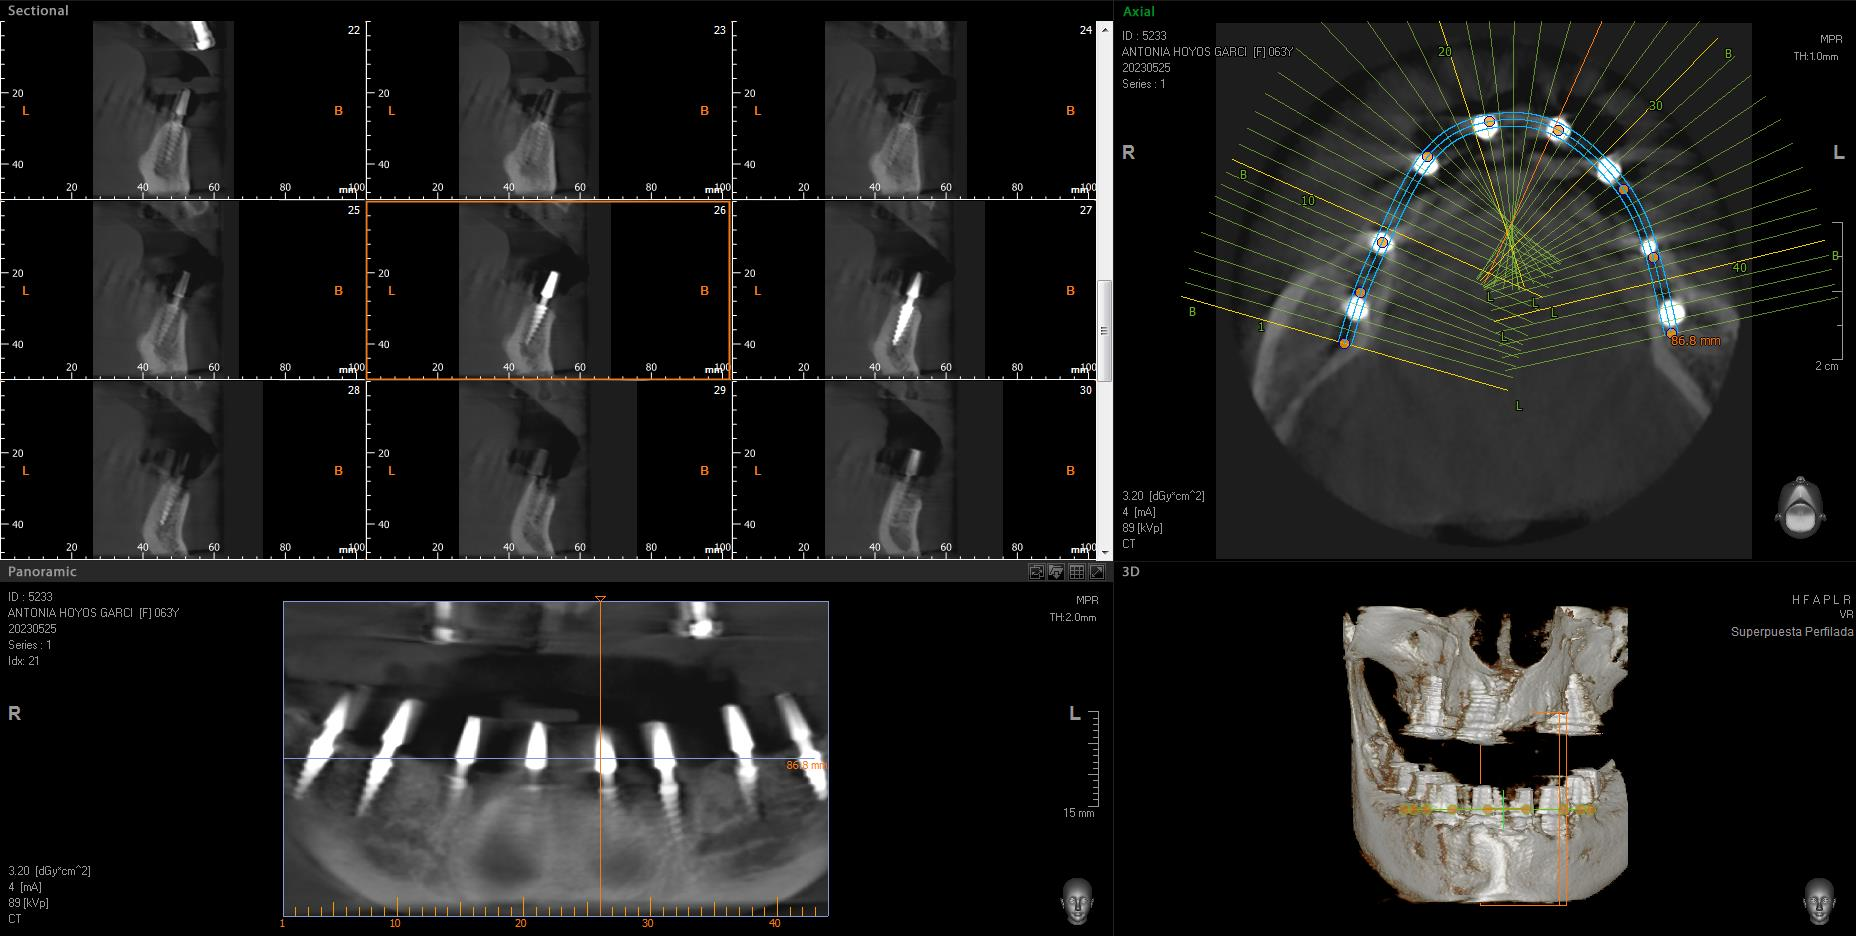

Implantes SLD-c

Secuencia de imágenes RX, antes y después de la inserción de implantes SLD-c en la parte inferior de la boca.

Paciente mujer de 65 años.

- Radiografía previa a la operación.

- Colocación implantes Radhex SLD-c parte inferior.

- Colocación implantes Radhex SLD-c parte inferior con soldadura.